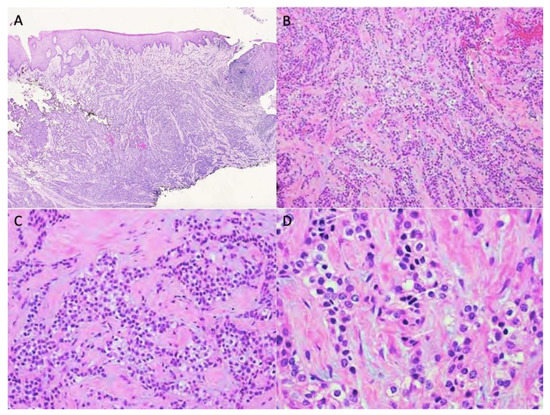

| Staining/IHC | PAS (+) D-labile Mucicarmine (−), p63 (+) CK5/6 (+), CK19 (+) | PAS (+) D-labile Mucicarmine (−) CK5/6 (+) | H&E only |

| Morphology | Infiltrative, non-encapsulated malignant neoplastic odontogenic epithelial proliferation with clear cell component in a dense fibrous connective tissue stroma. Neoplastic cells arranged in anastomosing trabeculae. Nuclear hyperchromasia and pleomorphism surrounded by clear, vacuolated cytoplasm. Stroma was hyalinized, densely collagenized, hypocellular, and hypovascular. | Neoplastic odontogenic epithelial proliferation diffusely infiltrated the connective tissue stroma. Neoplastic cells arranged in islands of variable size, trabeculae, and nests. Nuclei were hyperchromatic, central, and pleomorphic surrounded by clear cytoplasm. | Infiltrative odontogenic epithelial neoplasm intermixed with eosinophilic dentinoid matrix. Neoplastic cells arranged in infiltrative, non-encapsulated sheets, cords, and nests of polygonal cells with central hyperchromatic and slightly pleomorphic nuclei surrounded by clear cytoplasm and occasional pale eosinophilic cytoplasm. Occasional mitotic figures were noted. Neoplastic epithelial sheets and cords blended with eosinophilic cellular matrix without cellular rimming consistent with dentinoid deposits. |